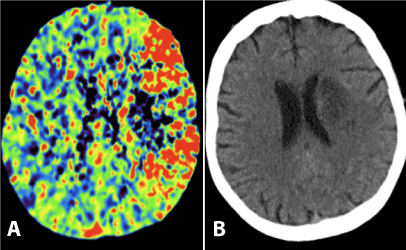

| Figure 2: Comparison between MTT (A) and NCCT of the brain (B) 6 days post event. Those images demonstrate infarction in the left centrum semiovale in the same region of the decreased MTT on the initial perfusion studies. The majority of the territory with increased MTT was not infarcted suggesting salvaged penumbra. |